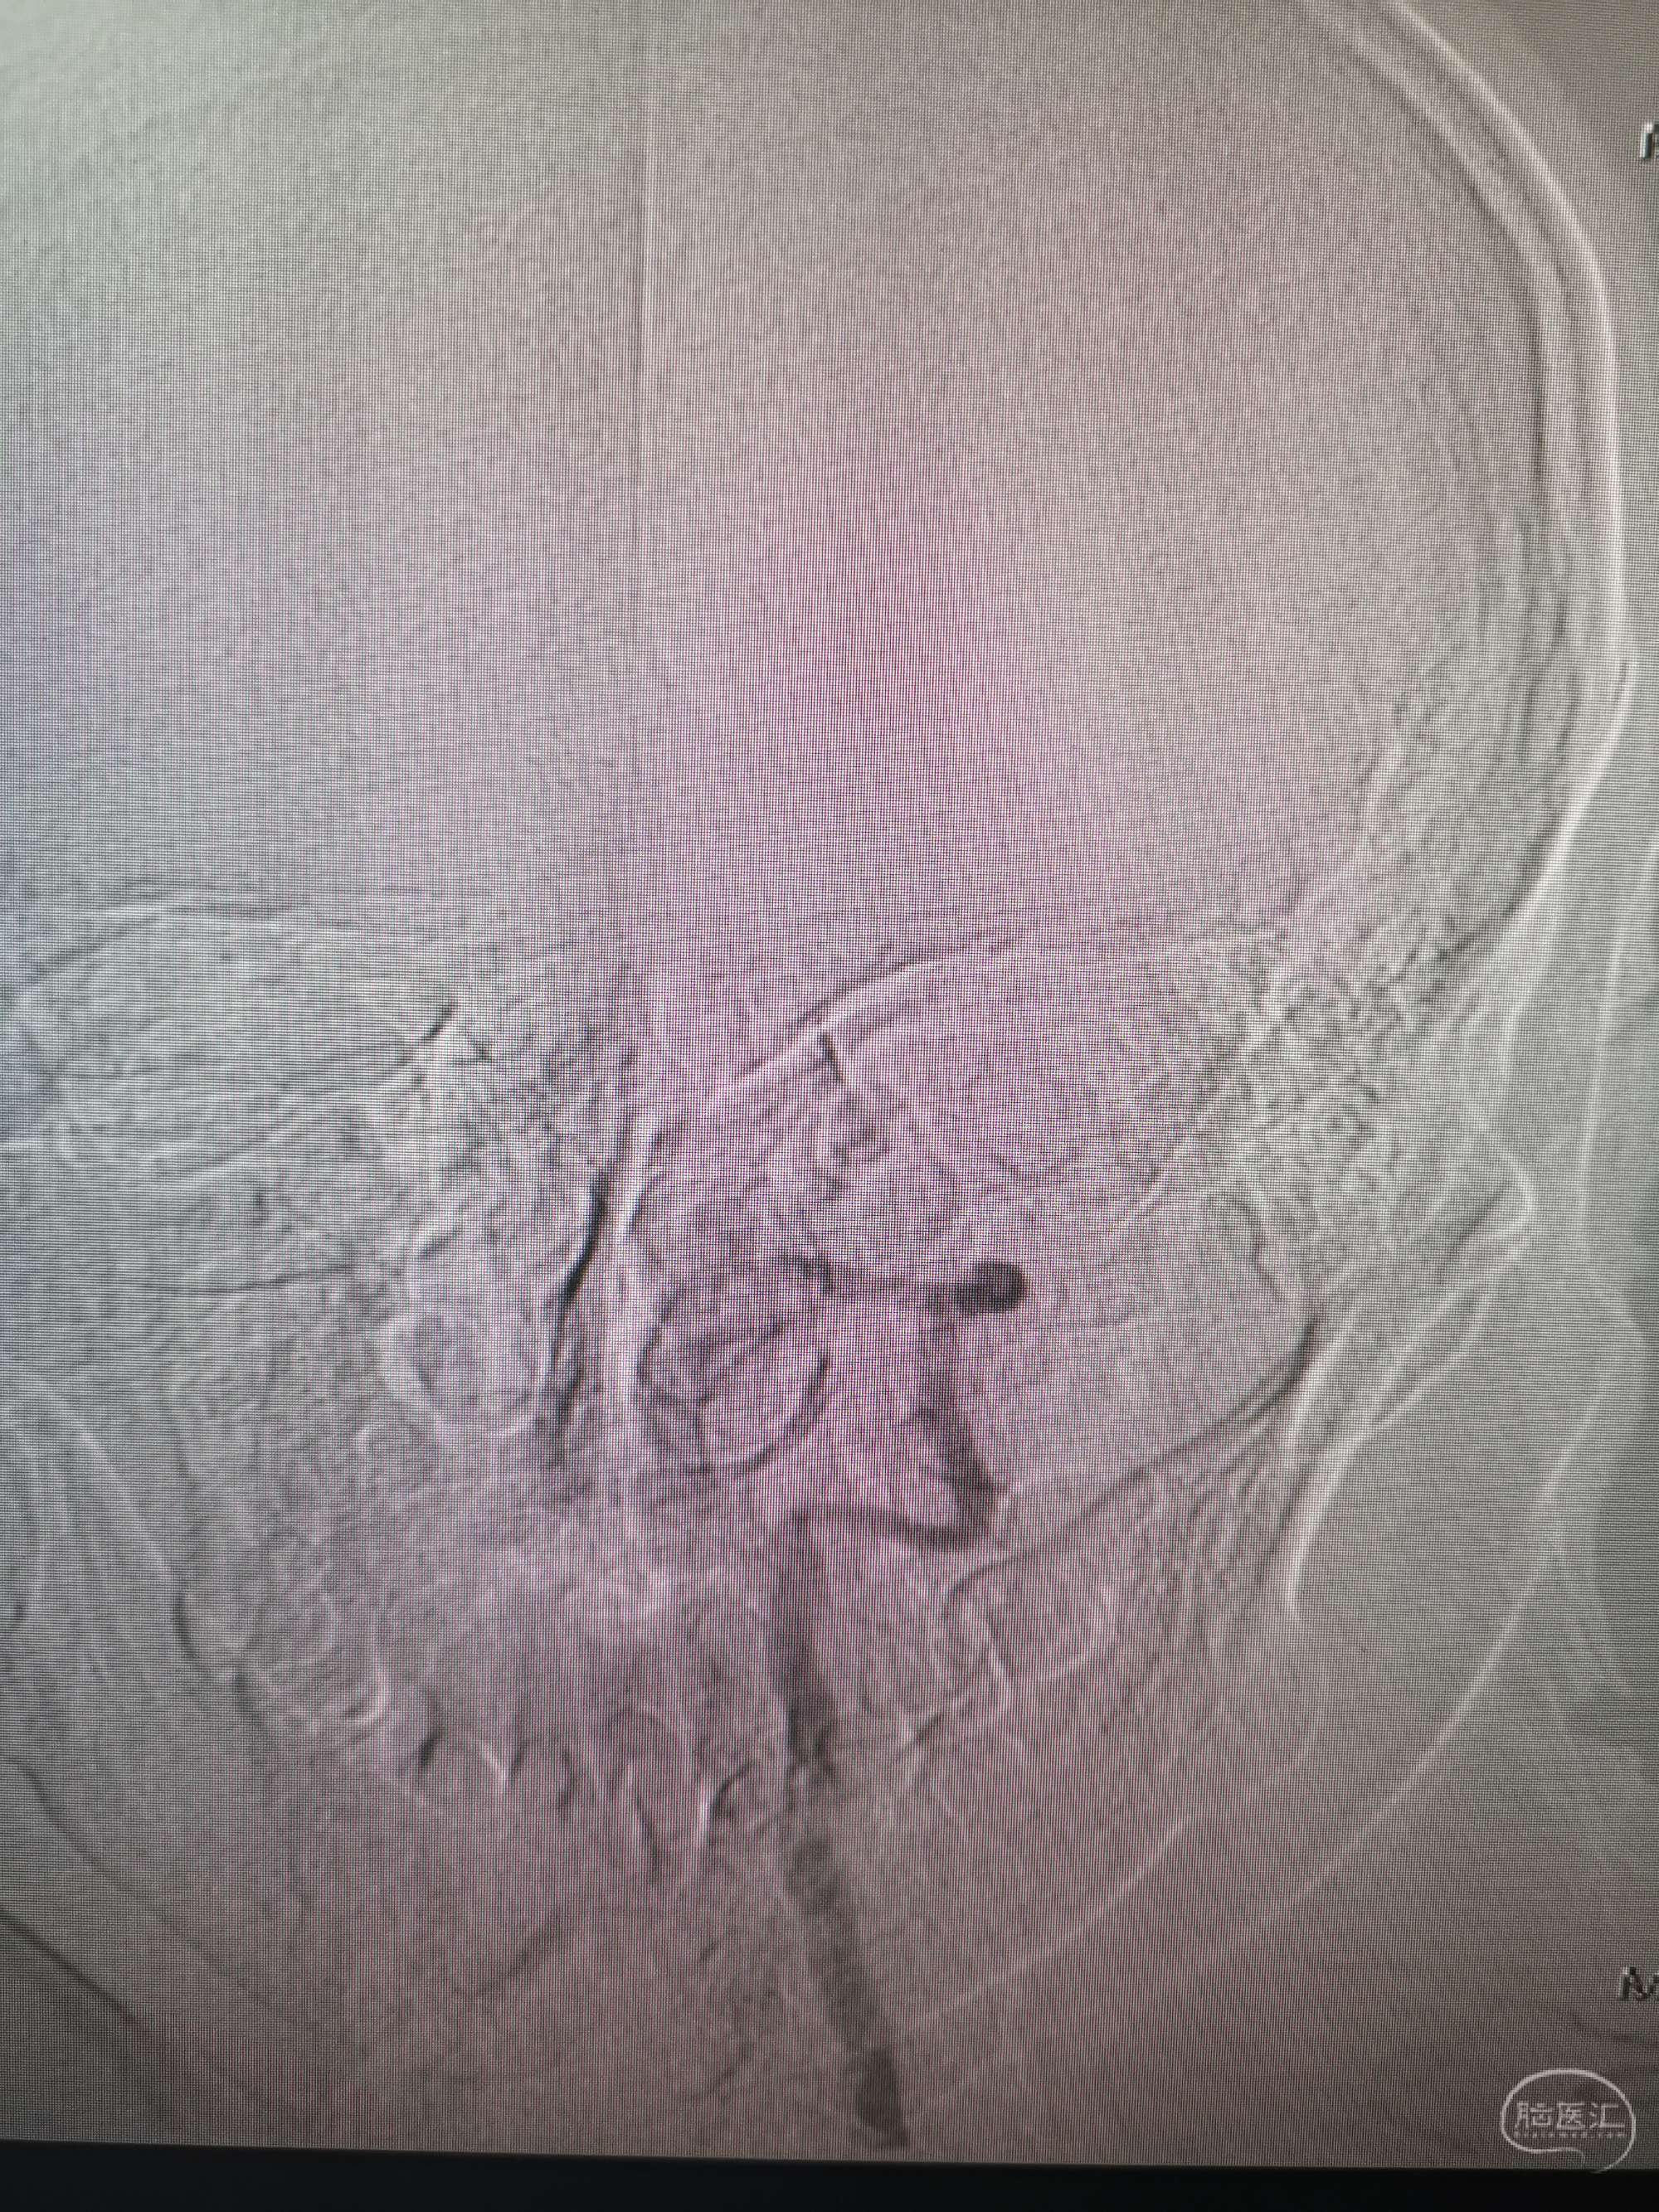

术前再次造影评估

右侧椎动脉穿支供血及左侧PICA供血较入院时略有改善,但改善不明显。故按计划行左侧椎动脉再通术